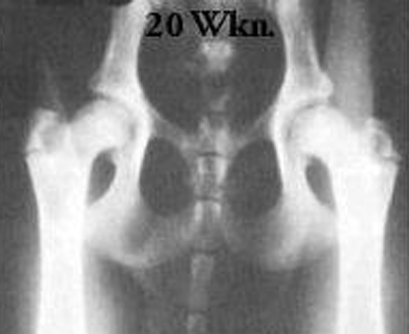

RTG znázorňujúce vývoj kĺbov v štenacom veku.

Vek psa - 20 týždňov

w heupen pup 20 wk oud